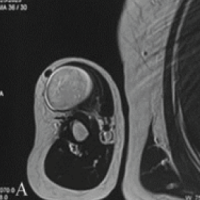

Radical tenosynovectomy was performed, with careful identification and preservation of the neurovascular bundles of the third digit (Fig. 3).

Figure 3: Flexor tendon of the left third finger following fasciectomy and synovectomy showing the neurovascular bundles of the third finger (white arrows).